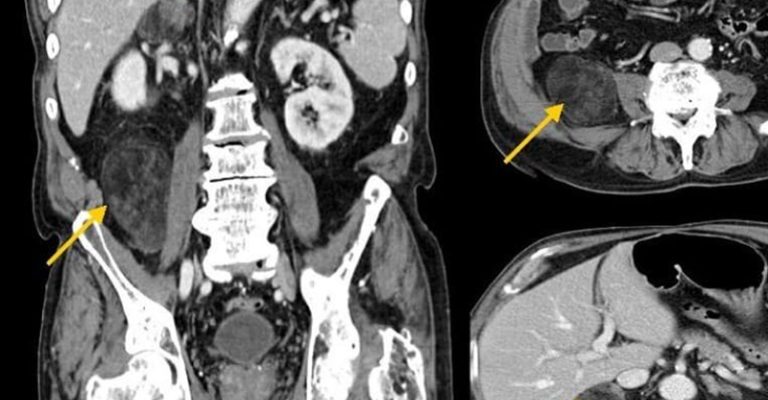

Batın MR, karın bölgesindeki organların manyetik rezonans görüntüleme yöntemiyle detaylı bir şekilde incelenmesini sağlayan bir tıbbi tetkiktir. Manyetik alanlar ve radyo dalgaları kullanılarak, vücut içindeki yumuşak dokuların net ve ayrıntılı görüntüleri elde edilir. Bu yöntem, karaciğer, böbrekler, pankreas, bağırsaklar, dalak gibi organların yanı sıra, karın boşluğundaki damar ve lenf düğümlerini de incelemekte kullanılır.

Batın MR, karın bölgesindeki organ ve dokuların detaylı incelenmesi gerektiğinde çekilir. Doktorlar, karaciğer hastalıkları, pankreas sorunları, böbrek anomalileri, bağırsak iltihaplanmaları veya tümörleri gibi durumları teşhis etmek amacıyla batın MR’ı tercih edebilirler.

Batın emarı, karın bölgesinde açıklanamayan ağrı, kitle veya anormallik tespit edildiğinde çekilir. Özellikle, karaciğer yağlanması, hepatit, safra kesesi taşları, pankreatit gibi durumlar araştırılırken kullanılır. Aynı zamanda, kronik böbrek hastalıkları, bağırsak hastalıkları ve karın içi enfeksiyonlar gibi durumların değerlendirilmesinde de önemli bir araçtır.

Batın MR, karaciğer sirozu, hepatit, pankreas kanseri, safra kesesi taşları, böbrek kistleri ve tümörleri, bağırsak tıkanıklıkları ve iltihaplanmaları gibi birçok hastalığın teşhisinde kullanılır.

Batın MR, karın bölgesindeki organ ve dokuların detaylı görüntülerini sağlayarak, birçok hastalığın ve anormalliğin tespit edilir. Bunlar arasında karaciğer, böbrekler, pankreas, bağırsaklar, dalak ve safra kesesi gibi organların yapısal özellikleri ve işlevsel durumları yer alır.